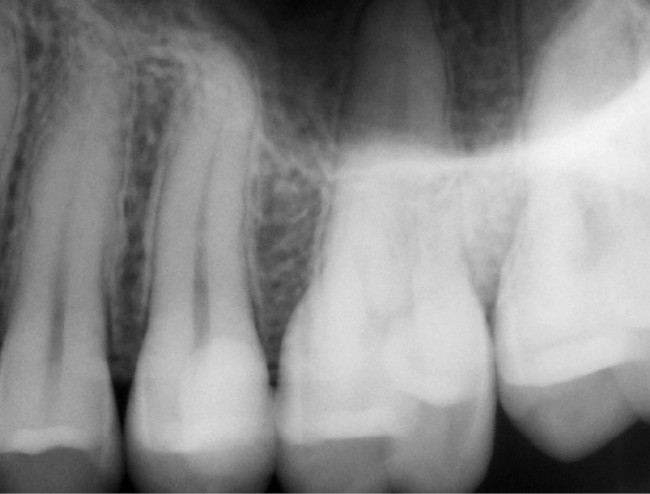

Si l’étude de Peters [18] nous montre que l’instrumentation laisse 35 % du volume canalaire non instrumenté, Ricucci et Siqueira montrent que la préparation physico-chimique n’élimine que partiellement les tissus nécrotiques à l’entrée des canaux latéraux, des isthmes et des ramifications apicales, en laissant des tissus enflammés et infectés, en association avec des lésions apicales [29] (fig. 4 et 5).

Fig. 4 – Coupe d’une racine mésiale de molaire mandibulaire avec deux canaux traités. Coupe à 3 mm de l’apex, coloration Brown et Brenn, technique modifiée par Taylor. Ces images montrent un isthme étroit avec une infection bactérienne, ce qui prouve l’importance de désinfecter et d’inclure l’isthme dans les traitements conventionnels et dans les rétropréparations apicales en chirurgie endodontique.